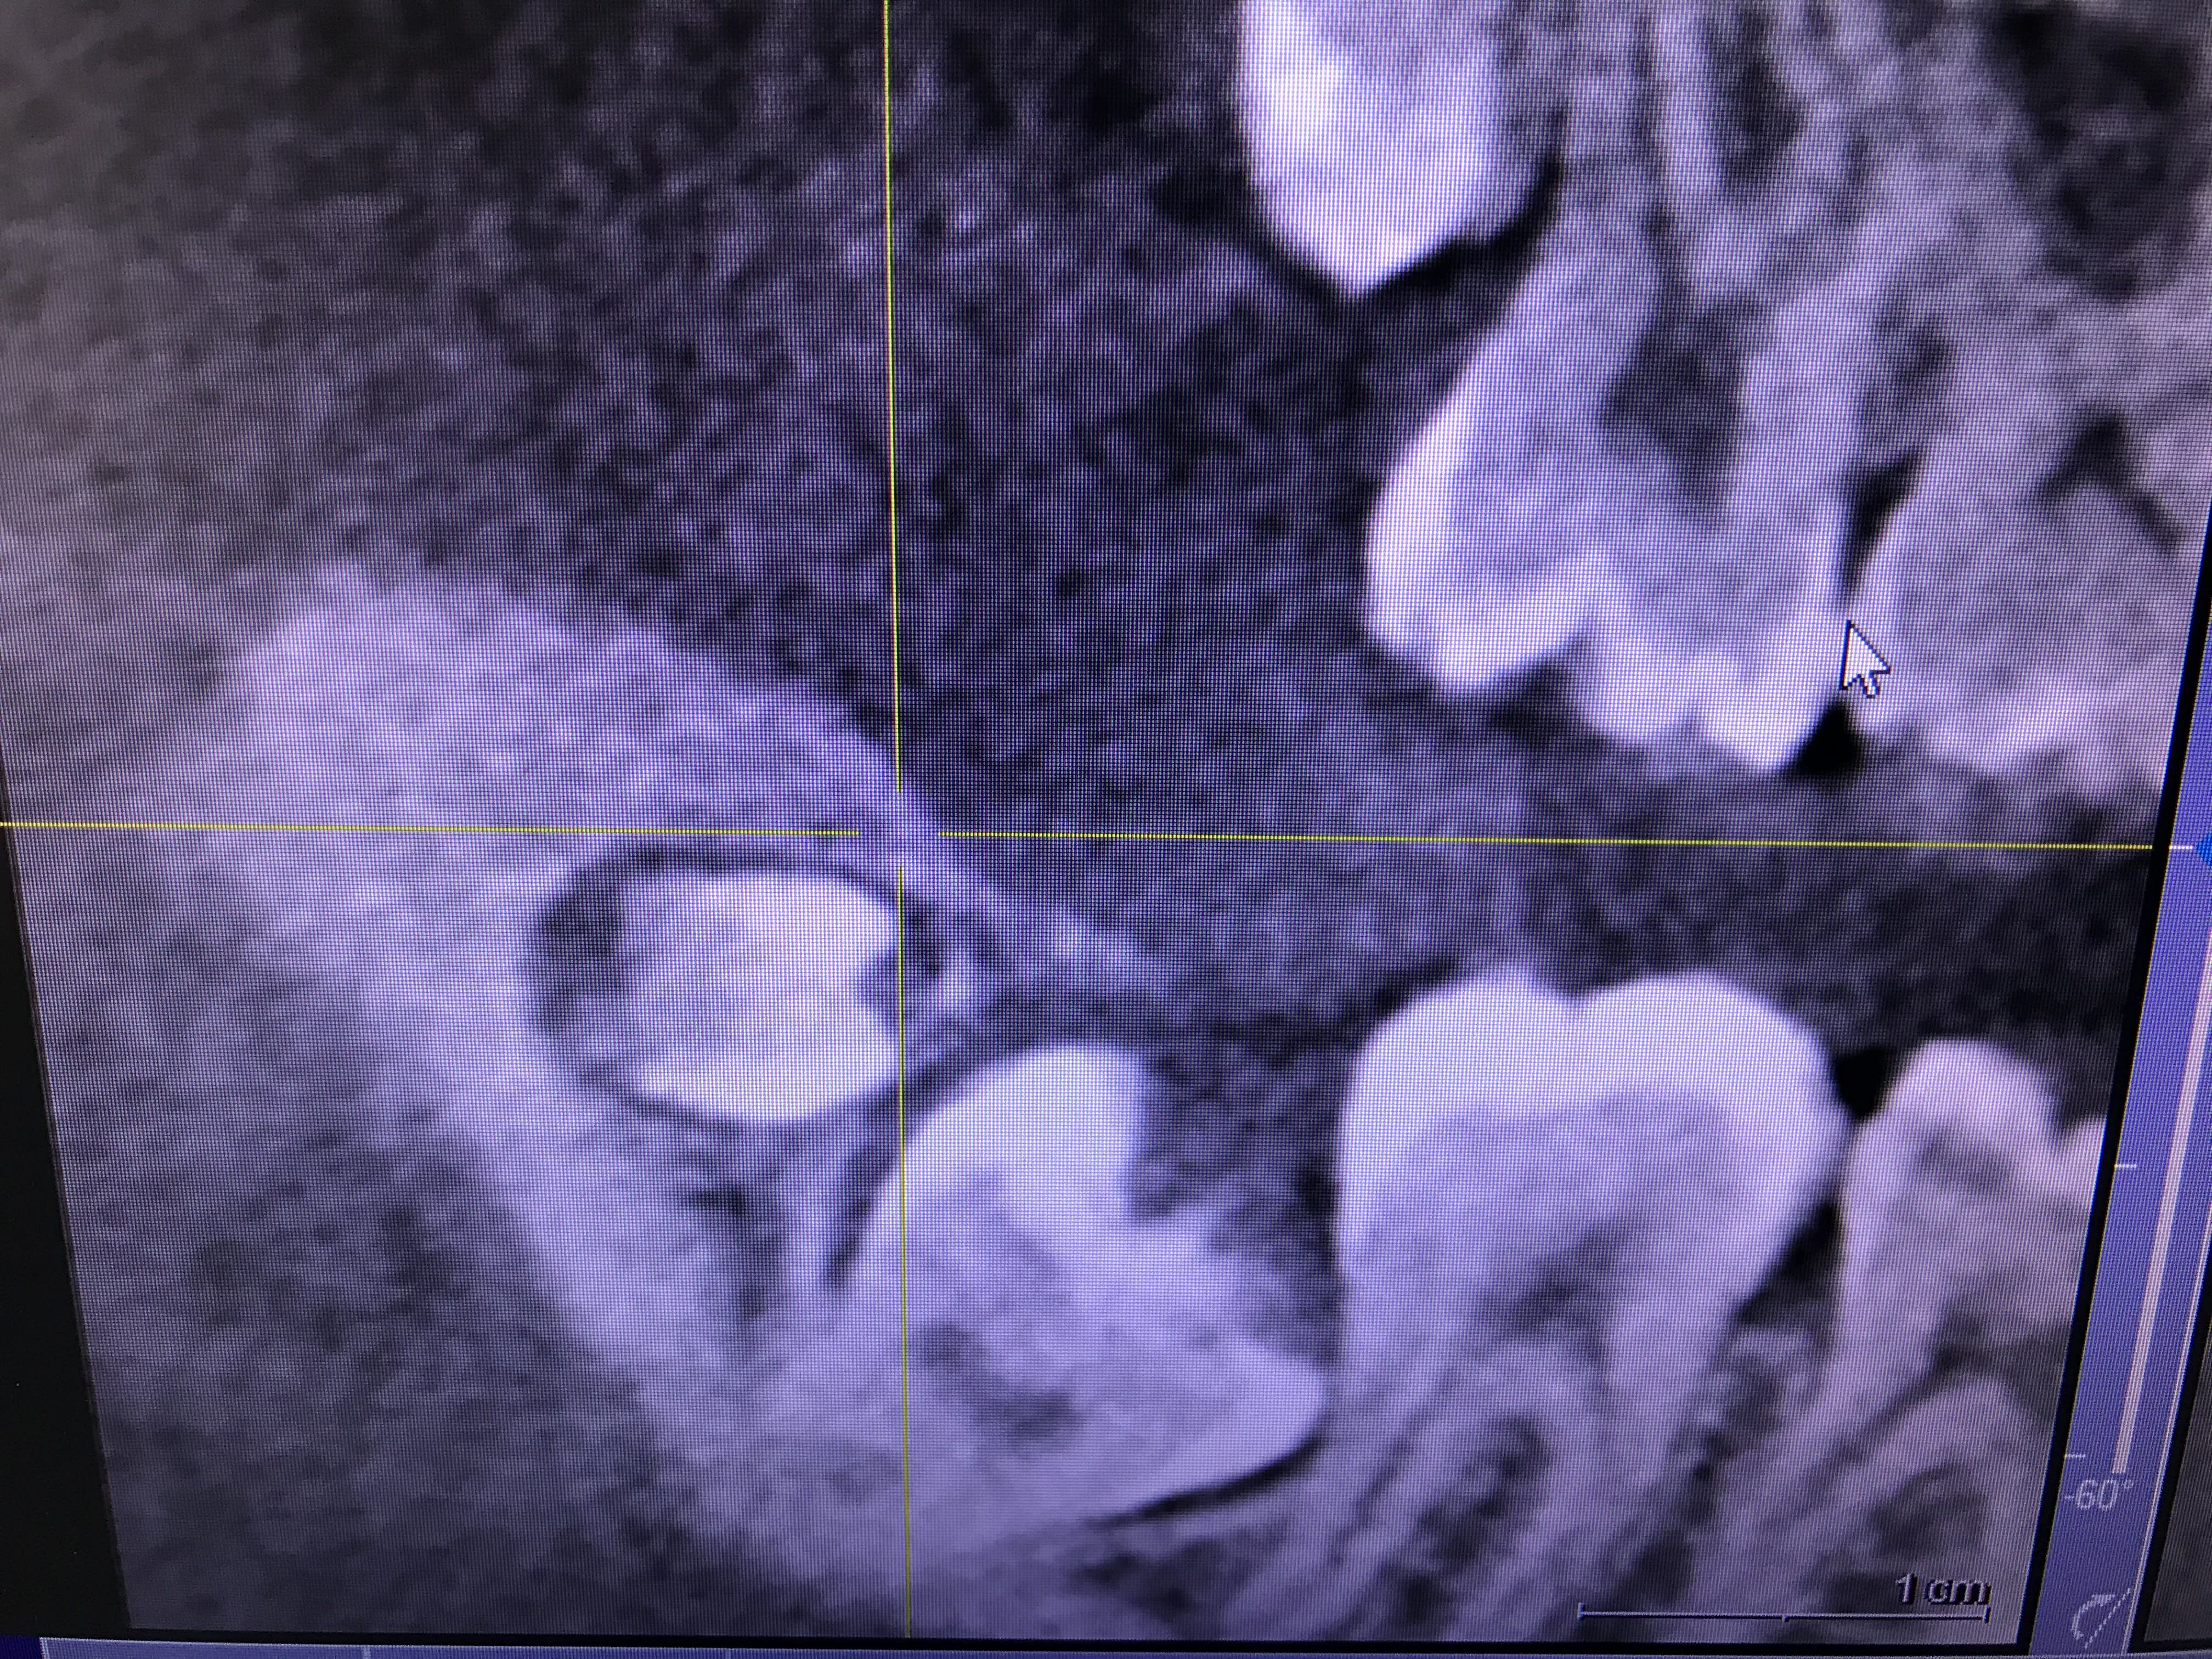

Voir des 19/29 plus rarement 39/49 c'est pas non plus si exceptionnel ..

Dans la même veine, souvent à la pano découverte fortuite de prémolaires mandibulaires surnuméraires incluses.